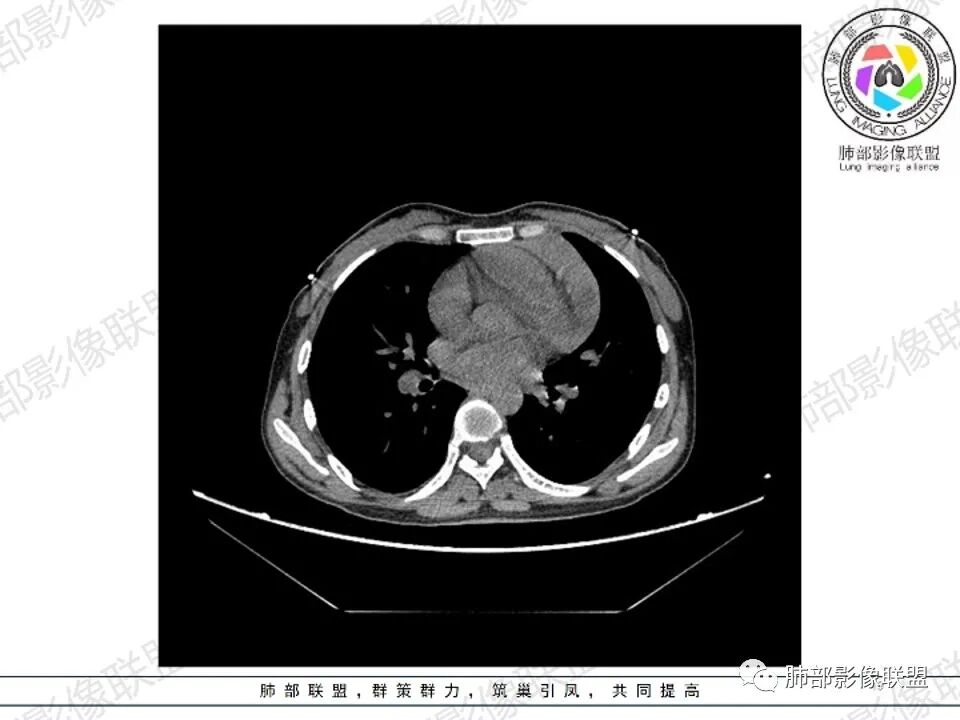

女,27,间断头晕、乏力3年,左眼视物模糊2月。贫血。胸部CT:前纵隔不规则肿块,多结节融合,边界不清,沿主动脉及肺动脉间隙生长,平扫密度欠均匀,增强扫描可见多发低密度坏死,纵隔血管供血穿行,腋窝多发大小不等淋巴结肿大。考虑恶性病变,胸腺癌?肉瘤?淋巴瘤?鉴别胸腺瘤、结节病等。

临床:年轻女性,慢性病程,多系统病变,头晕,贫血,视物模糊。

CT:定位纵膈病变,前中纵隔多发肿块,质软,塑形,密度不均匀,边界清楚。增强不均匀强化,坏死边界清楚,血管漂浮征。双侧腋下多组淋巴结肿大,明显异常强化。

2.影像显示前纵隔不规则块状影,依势贴附心脏大血管旁,密度不均,边界不甚清楚,有结节融合感。

3.病灶轻度不均匀强化,可见血管穿行,散在液性低密度区。

双肺门未见肿大淋巴结。

4.双侧腋窝区见增大淋巴结,边界清楚。